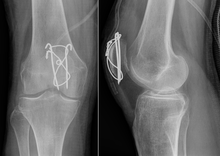

Patellar Fractures (Broken Kneecap

Patellar Fractures (Broken Kneecap

Knee Pain: Causes, Treatment, and When direct fall on knee cap

Patella Fracture | Reno Orthopedic Center direct fall on knee cap

patella hairline fracture? - Quora direct fall on knee cap